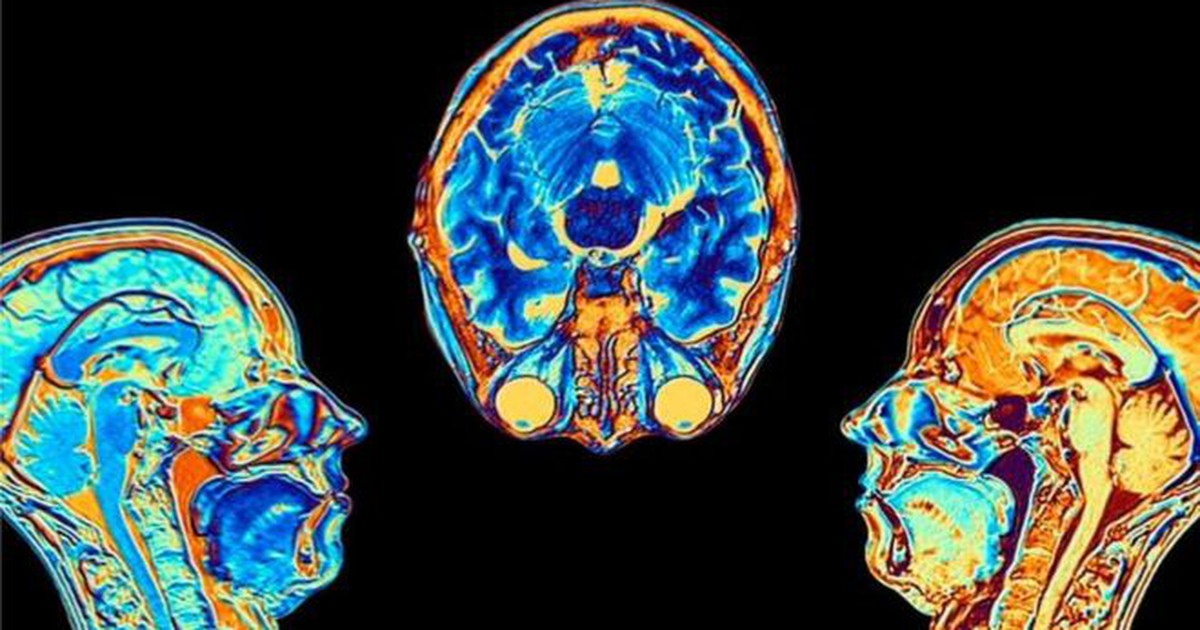

Phim chụp MRI não trước và sau khi nhiễm Covid -19 cho thấy những thay đổi cấu trúc trong não, khác với người không nhiễm bệnh, theo trang web y tế Verywell Health (Mỹ).

Chàng trai Alex Bishop (24 tuổi, ở Anh) đã trải qua 15 tháng vật lộn với hậu Covid-19 . Anh trước đây từng bị chấn thương não. Tình trạng viêm nhiễm đã tấn công chấn thương này, khiến anh phải tốn đến 13.000 USD (gần 300 triệu đồng) để điều trị.